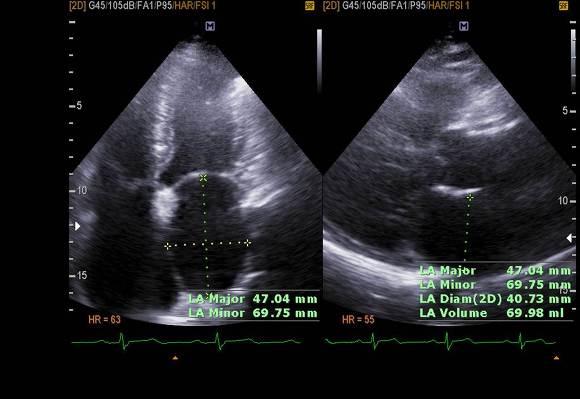

pic 5. LA enlargement (almost 70ml) also RA enlarged